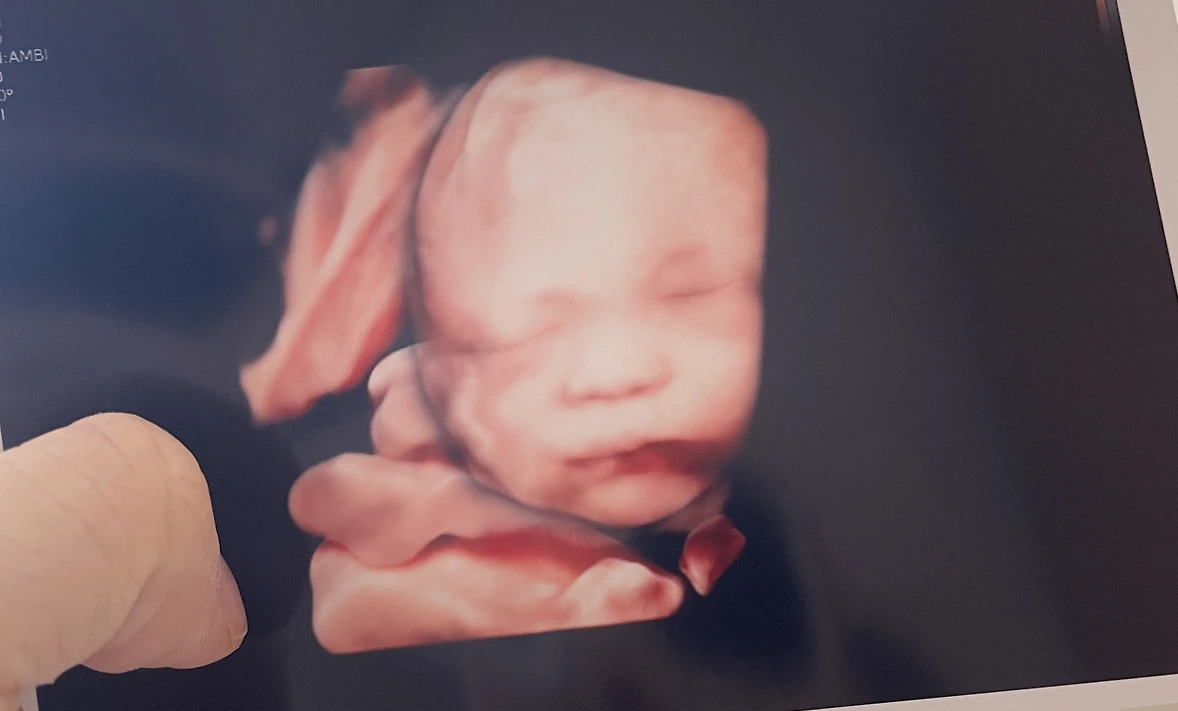

병원에서 예쁜 십자가도 선물 받아서, 손에 꼭 쥐고 기도했다. 아가 초음파 사진을 또 주셨는데, 좀 더 컸고, 좀 더 웃기게 생겼지만, 더 많이 사랑스러워졌다. 나를 하나도 안 닮고 남편이랑 똑같이 생겨서 웃음이 났다.